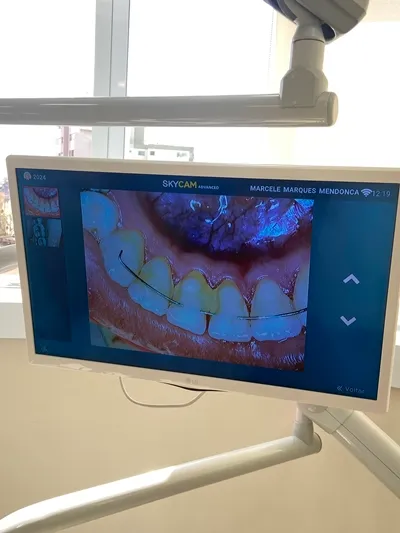

Há mais de 20 anos a Dra. Marcele cuida do sorriso e da auto-estima das pessoas. Localizada no centro de Viçosa, próximo ao Alfa Hotel, nosso espaço acolhedor e com tecnologia de ponta oferece procedimentos odontológicos precisos e confortáveis. Nossa equipe experiente está pronta para cuidar da sua saúde bucal e ajudá-lo a alcançar o sorriso dos seus sonhos. Na MM Odontologia, não apenas cuidamos da sua saúde bucal, mas também nos dedicamos a restaurar sua auto-estima e bem-estar.